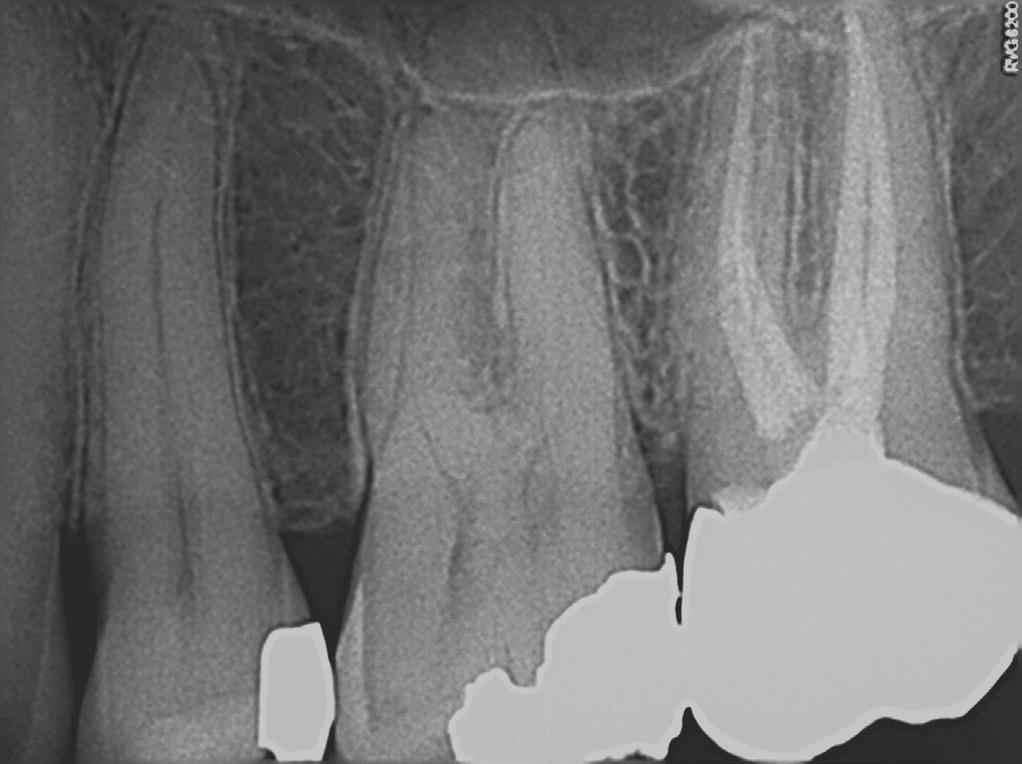

A periapical radiograph and a limitedfield-of-view cone beam computed tomogram of teeth 14 and 15 were taken, and no radiographic signs of apical periodontitis related to these teeth were noted that day (Fig 1). Sensibility tests were also performed. Tooth 15 responded normally to palpation and to bite and felt “different” on percussion (not painful, which is an important distinction to make). Tooth 14 responded

normally to palpation, percussion, and bite. Cold placed on tooth 14 triggered a significantly elevated, throbbing response that lingered more than 1 minute. Of all the tests performed, the cold on tooth 14 most closely replicated the pain of her chief complaint.

At our final appointment, I was able to fully instrument the MB1 canal. The final postoperative radiograph shows the curvature of the MB1 canal of tooth 14 (Fig 2). The teeth were closed with a medicated sponge and provisional material, and the patient was referred back to her general dentist for restoration of these teeth.

Fig 2. Postoperative radiograph of teeth 14 and 15.

Fig 1. Preoperative radiographs. A. Tooth 14. B. Tooth 15.